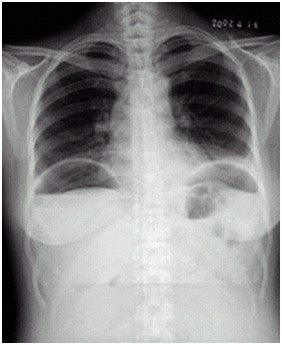

04卷-4.病史:女性,42歲,腹痛1天,進行性加重。診斷(本題滿分2.00分)

A.腸梗阻

B.腸結(jié)核

C.正常腹平片

D.消化道穿孔

本題答案:D

【該題針對“ X線-消化道穿孔 ”知識點進行考核】